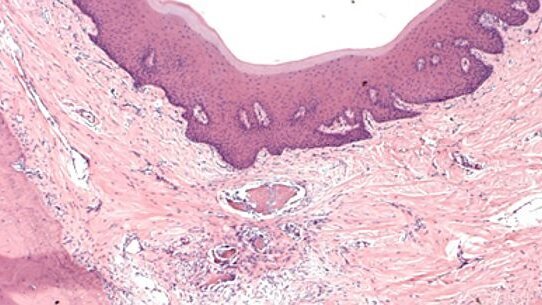

Principles of orthodontic biomechanics are usually taught with the help of a typodont, consisting of artificial teeth embedded in wax. This set-up ignores entirely the biological aspect of tooth movement. However, in the clinical setting, living patients are encountered, and mechanical forces mobilize their teeth. These movements result from the development of strains in dental and paradental tissues, followed by modelling and remodelling of these tissues.

In some patients systemic conditions may exist, evoking complications such as root resorption, dehiscences and fenestrations of the alveolar bone. Hence, clinical orthodontics must be viewed as a specialty staunchly entrenched in biology, all the way to the molecular level. As a clinical profession, it must be based on a commanding knowledge of mechanics, biology, physiology, and pathology. The goal of this article is to enhance the biological awareness of the orthodontic practitioner, in order to minimize or avoid tissue damage during orthodontic treatment. It will demonstrate that this objective may be achieved by closely focusing on the nature of root movements, and avoiding dogmatic following of “prescription” methods that promise “automatic” correction of all malocclusions.